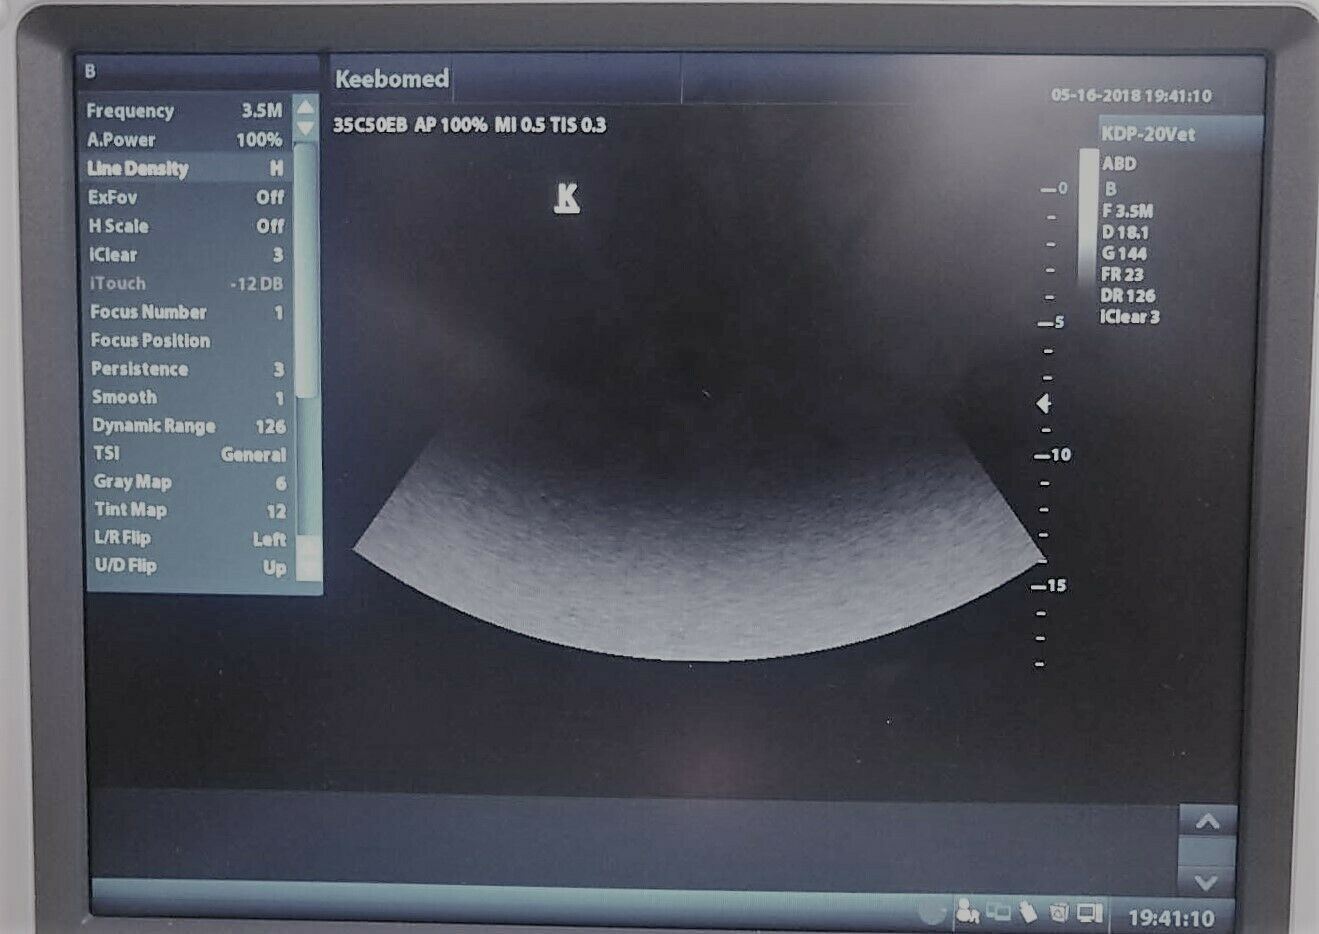

Keebomed K-DP-20 is equipped with a best-in-class combination of performance and affordability. Provides the latest imaging technologies and convenient workflow options. Offers abundant measurement packages covering traditional ultrasound applications and emerging fields such as urology, MSK, and anesthesia.

- Tissue Harmonic Imaging (THI) enhancing contrast resolution

- Quick image optimization by IP(Image Processing)

- 8-segment TGC allowing delicate image adjustment